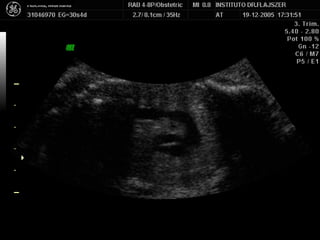

Evaluación del corazón fetal en la ecografía obstétrica Modo B ¿CUANDO? Segundo y tercer trimestres ¿Como? De mayor a menor

1) LONGITUDINAL / CEFALICA / DORSO IZQ

Apex y estómago: ¿Cerca o lejos del transductor? Lejos Long/Cef/D.izq